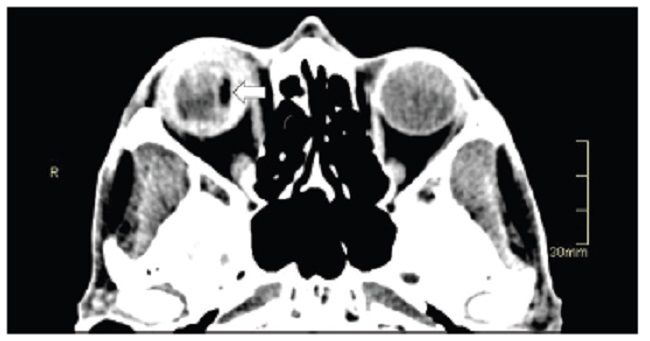

Las calcificaciones oculares y el material médico se pueden confundir con cuerpos extraños u otras lesiones orbitarias1. Las localizaciones típicas de las calcificaciones permiten diferenciarlas de cuerpos extraños hiperdensos. Las más frecuentes son las calcificaciones trocleares, las placas esclerales, las drusas del nervio óptico y la ptisis bulbi. Las primeras tienen localización superomedial dentro de la órbita (Fig. 13), en la tróclea del músculo oblicuo superior, aunque se pueden observar en todas las edades, hay mayor prevalencia de calcificaciones trocleares en pacientes con enfermedades autoinmunes y niveles elevados de fosfatasas alcalinas. Las placas esclerales se localizan en los sitios de inserción de los músculos rectos medial y lateral (Fig. 14) y son más comunes en los pacientes ancianos. Las calcificaciones que ocurren cerca del disco óptico se conocen como drusas del nervio óptico (Fig. 15), las cuales se asocian a degeneración macular y pueden ser causa de pseudopapiledema benigno. La ptisis bulbi es una atrofia y calcificación del globo ocular como secuela de enfermedades infecciosas, inflamatorias o traumáticas previas (Fig. 16) (1,11. Los imitadores de lesiones abiertas del globo ocular incluyen las deformidades como coloboma, estafiloma y el globo ocular elongado por glaucoma o miopía (Fig. 17). Las masas orbitarias y los hematomas también pueden alterar el contorno del globo ocular y asociarse a calcificaciones o relacionarse con desprendimiento de retina (Fig. 18) (1,6,8,11.